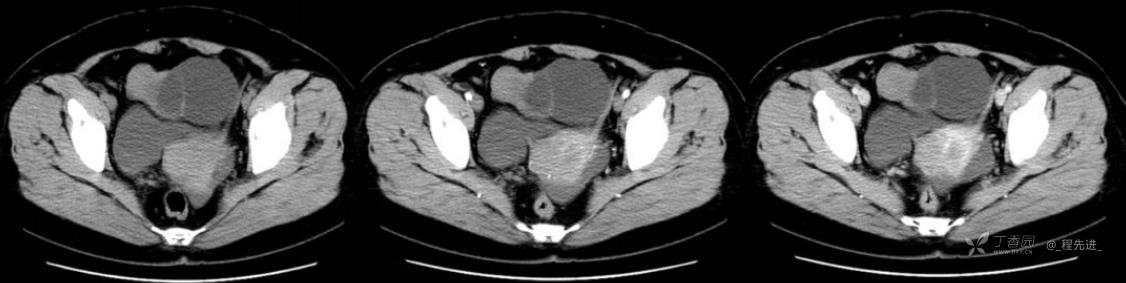

1月特别精彩病例|中老年女性,盆腔包块近半年持续增大【病理已公布】

患者年龄:53岁

简要病史:4年前体检时发现盆腔包块及子宫肌瘤,近半年复查盆腔彩超发现包块持续增大,近1年月经欠规律,伴腰、腹胀。

体格检查:宫颈举痛(+),子宫增大,质地中等,活动可,无压痛;右下腹轻压痛,无反跳痛,左侧附件区未扪及明显包块,无压痛。

阴式彩超:子宫约65*58*44mm大小,子宫肌层可见多个低回声块影,较大的为35*27mm(位于子宫前壁下段偏右侧壁),边界清,内回声欠均匀,后方回声衰减。考虑子宫多发肌瘤。子宫后壁可见一混合回声包块,大小约31*20mm,边界不清,内呈强弱回声,分布不均,考虑子宫腺肌瘤,其他疾患待删。子宫内膜厚6mm,宫颈可见多个囊性暗区,边界清,内透声好,后壁效应增强,较大的为15*11mm。子宫前方偏左侧可探及一大小89*75mm囊性肿块,边界清,壁薄光滑,内透声好,可见分隔光带